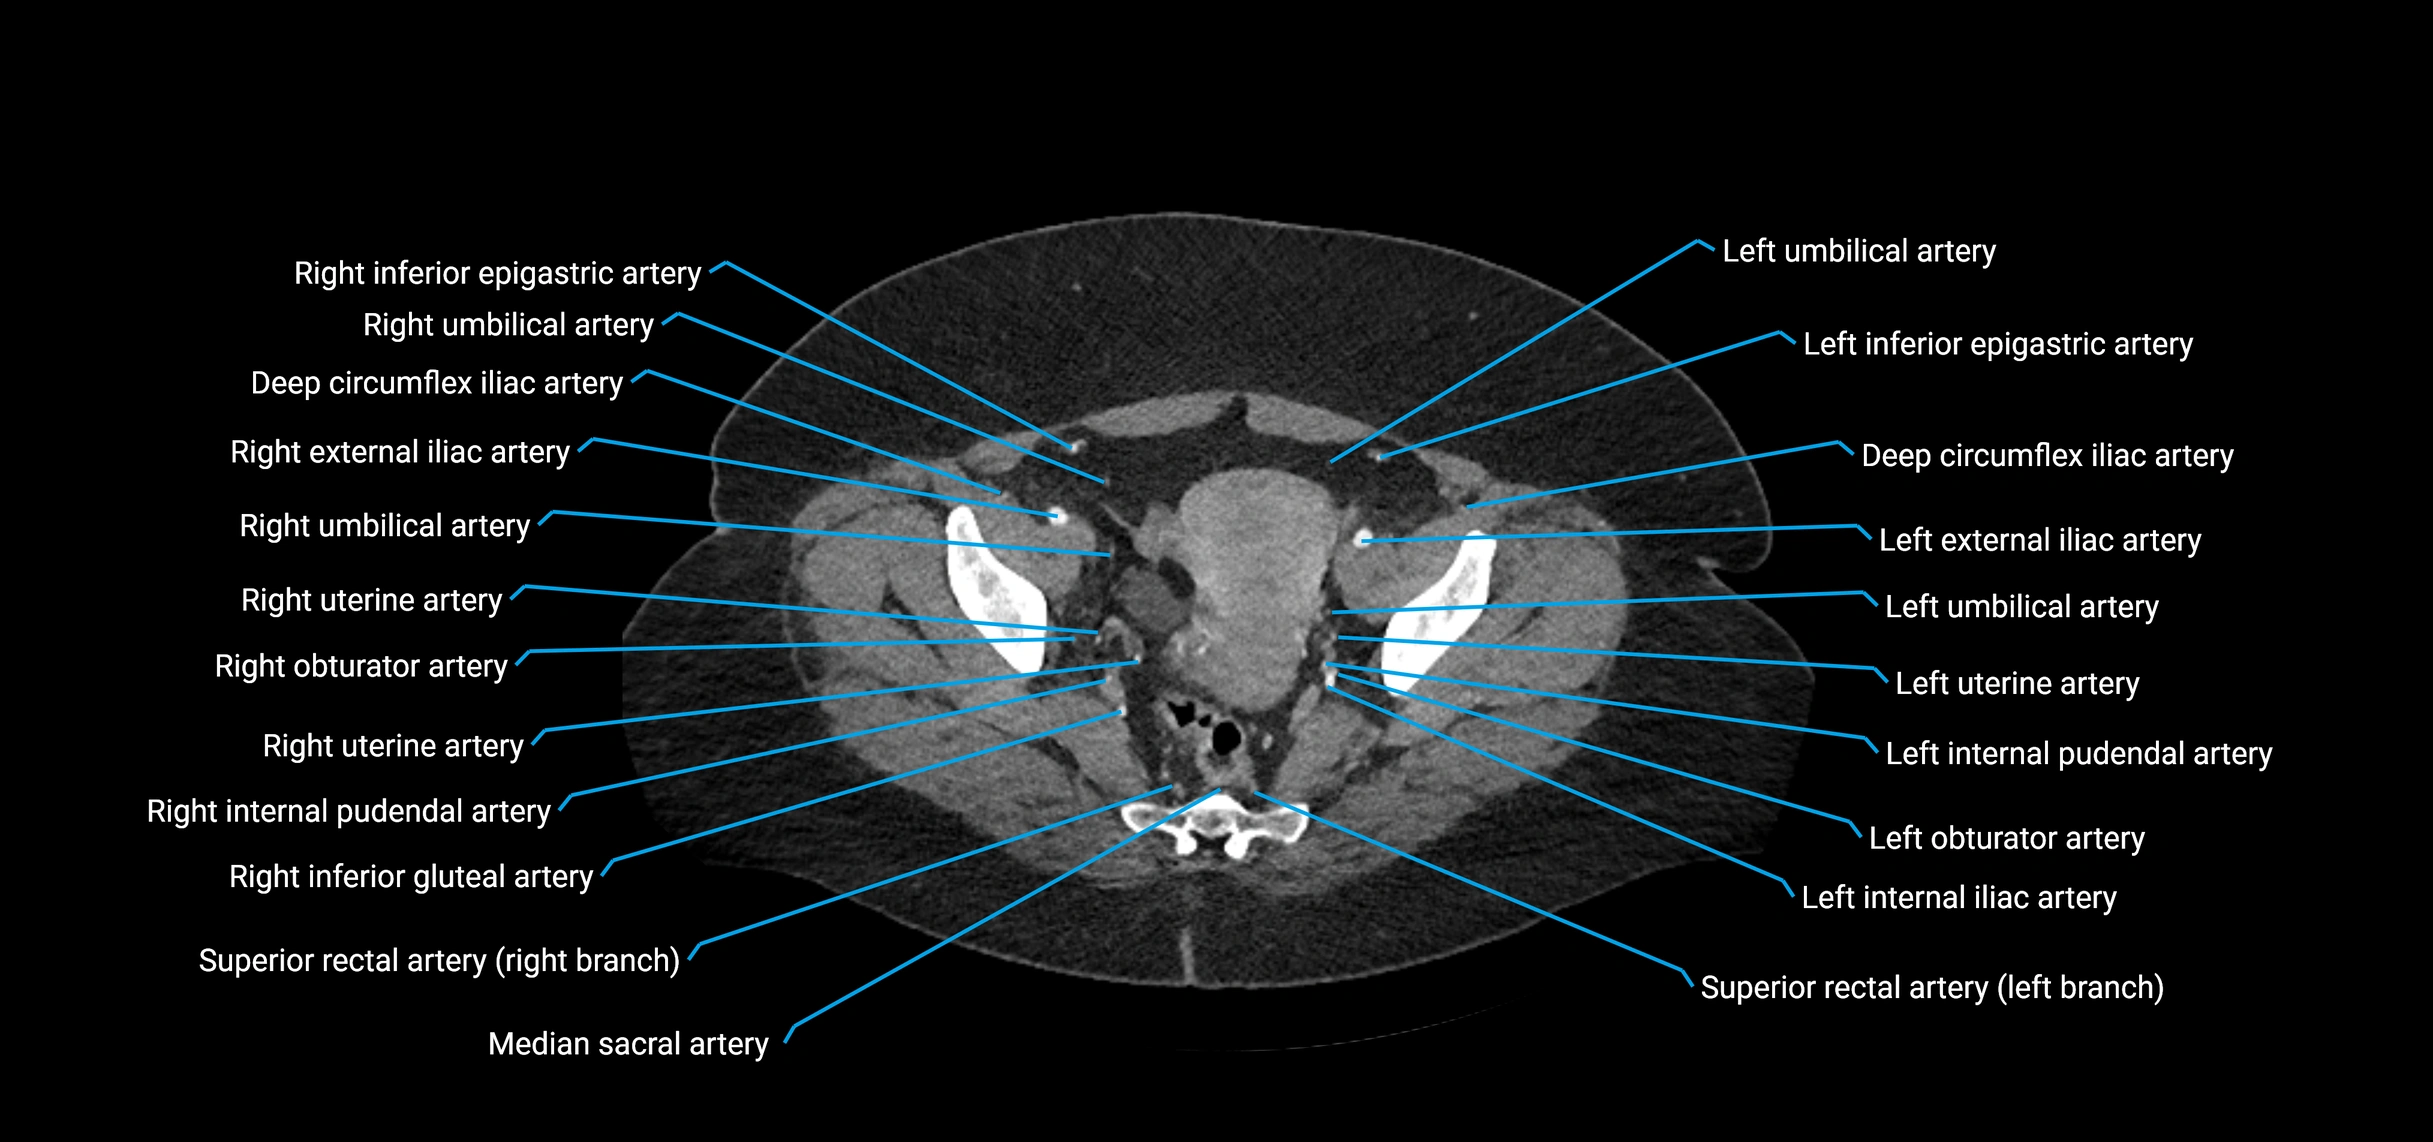

Contrast-enhanced CT (CTA):

• Gold standard for abdominal aortic imaging

• Provides excellent detail of lumen, wall, aneurysm, thrombus, and branch vessels

• Multiplanar and 3D reconstructions help in aneurysm measurement, stent graft planning, and dissection evaluation

• Detects acute rupture, traumatic injury, or occlusion with high sensitivity